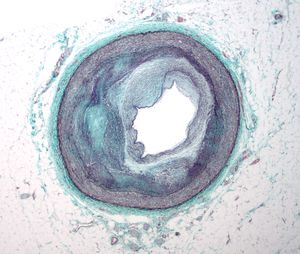

يمكن اعتبار مرض تصلب شرايين القلب مجموعة من الأمراض التي تصيب القلب. واحدة من هذه صور هذا المرض هو شخص بلا أعراض وجدران شرايين قلبه التاجية مبطنة من الداخل بخطوط من الدهون atheromatous streaks. يمثل ظهور هذه الخطوط المرحلة الأولى من مرض القلب التاجي ولكنها لا تعيق تدفق الدم خلال الشريان. إذا تم عمل تصوير الشرايين التاجية Coronary Angiogram خلال هذه المرحلة من المرض فانه من المحتمل ألا يظهر أي دليل على وجود مرض تصلب الشرايين القلبية وذلك لان قطر تجويف الشريان لم يقل. خلال عدة سنوات، تزداد هذه الخطوط الدهنية سماكة، وازدياد سماكتها مبطِنة جدار الشريان يؤدي في النهاية إلى صغر تجويفه وبالتالي يعوق مسار الدم خلاله. اُعتقد في السابق أن عملية تكوّن الصفائح الدهنية عملية بطيئة وتدريجية، لكن ظهرت دلائل حديثة على أن التكون التدريجي لهذه الصفائح يُسرّعُه تمزقات صغيرة تحدث فيها مما يؤدي إلى ازدياد حجم الصفيحة الدهنية نتيجة تراكم المواد المتخثرة عليها. من النادر أن تسبب الصفائح الدهنية التي تسد أقل من 70 في المائة من تجويف الشريان أعراض مرض انسداد الشرايين التاجية. في حال ازدياد حجم الصفيحة مسببة انسداد الشريان بنسبة تزيد عن 70 في المائة، تظهر في الشخص في هذه المرحلة أعراض انسداد الشرايين التاجية. يمكن القول في هذه المرحلة من المرض أن الشخص لديه مرض نقص التروية القلبية ischemic heart disease. تُلاحظ أولى أعراض مرض نقص التروية القلبية خلال الأوقات التي يزيد فيها الضغط على عمل القلب. كمثال على ذلك، الم الذبحة الصدرية الجُهدية exertional angina أو تراجع قدرته على تحمل التمارين البدنية. قد يتطور المرض فيما بعد ليصل إلى الحد الذي يُسد فيه تجويف الوعاء الدموي بشكل شبه كامل، معيقاً وصول الدم حامل الأكسجين إلى عضلة القلب. المصابون بهذه الدرجة من مرض الشريان التاجي يكونون قد عانوا من جلطة قلبية (ذبحة صدرية) مرة أو اثنتان، وقد يكون لديهم أعراض أو علامات مرض الشريان التاجي المزمن، متضمنا الم الذبحة الصدرية بدون أي مجهود بدني angina at rest أو الاستسقاء الرئويflash pulmonary edema. يجب أن يتم التمييز بين كلٍ من مرض نقص التروية القلبية myocardial ischemia والجلطة القلبية (احتشاء عضلة القلب) myocardial infarction. نقص التروية معناه أن كمية الأكسجين التي تصل إلى عضلة القلب غير كافية لتلبية احتياجه. عندما تنقص تروية عضلة القلب فإنها لا تعمل بالشكل الأمثل، وإذا نقصت التروية لمساحة كبيرة من عضلة القلب فان ذلك قد يؤدي إلى عدم قدرة العضلة على الانقباض والانبساط. إذا تحسن تدفق الدم إلى العضلة فان نقص التروية يمكن عكسه. بينما الجلطة القلبية معناها أن نسيج العضلة قد مات ولا يمكن عكس ذلك لقلة تدفق الدم المشبع بالأكسجين إليها. قد يحدث للشخص تمزق للصفيحة الدهنية في أي مرحلة من مراحل المرض. التمزق المفاجئ للصفيحة قد يؤدي إلى جلطة قلبية مفاجِئة (ذبحة صدرية).

فيسيولوجية مرضية خاصة